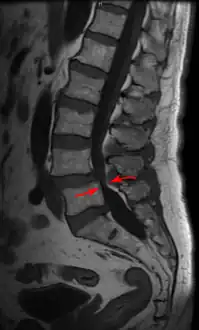

MRI of a lumbar spinal stenosis L4-L5. L4-L5 antherolisthesis of grade I. Hypertrophy of interspinous ligaments in relation to Baastrup's disease.